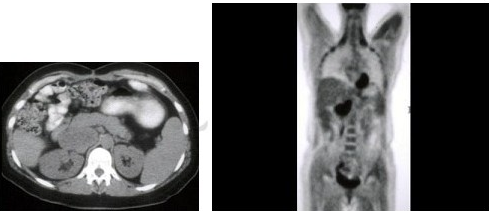

20、单项选择题

男,55岁,有结肠癌史,结合图像,最可能的诊断是()

A.肝转移

B.结肠癌复发

C.门静脉栓塞

D.十二指肠癌

E.以上都不是

21、单项选择题 X线检查左心房最有效的方法为()